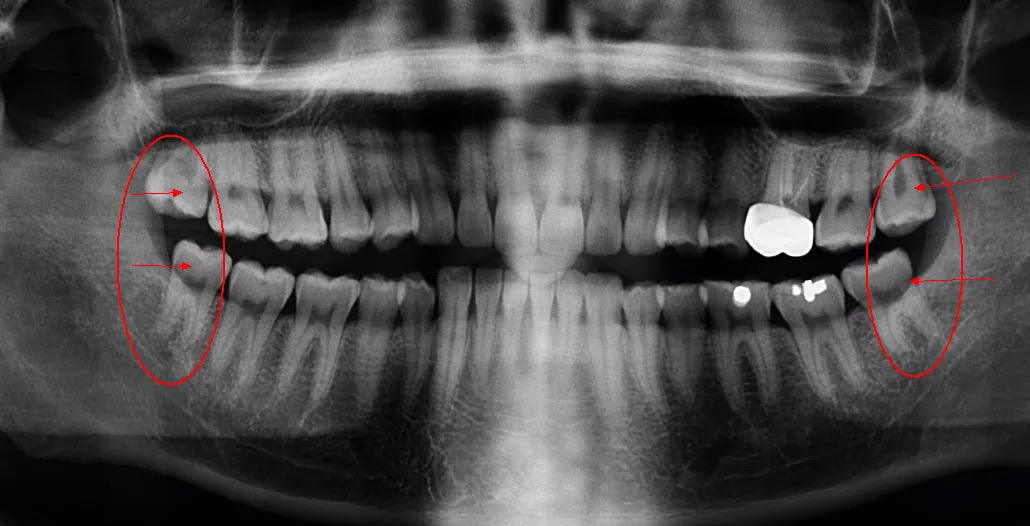

第三,智齿对邻牙造成严重影响。当智齿生长空间严重不足,更坏的可能是出现阻生智齿,即没有按正常垂直方向生长的智齿。阻生智齿不仅会引发自己 周边牙龈炎症,更有可能对邻牙施力,导致原本整齐的牙齿移位,甚至导致邻牙的龋坏,这就是医生常说的"好牙都被顶坏了",这种情况下当然要趁早就医,及时拔出,保住好牙。